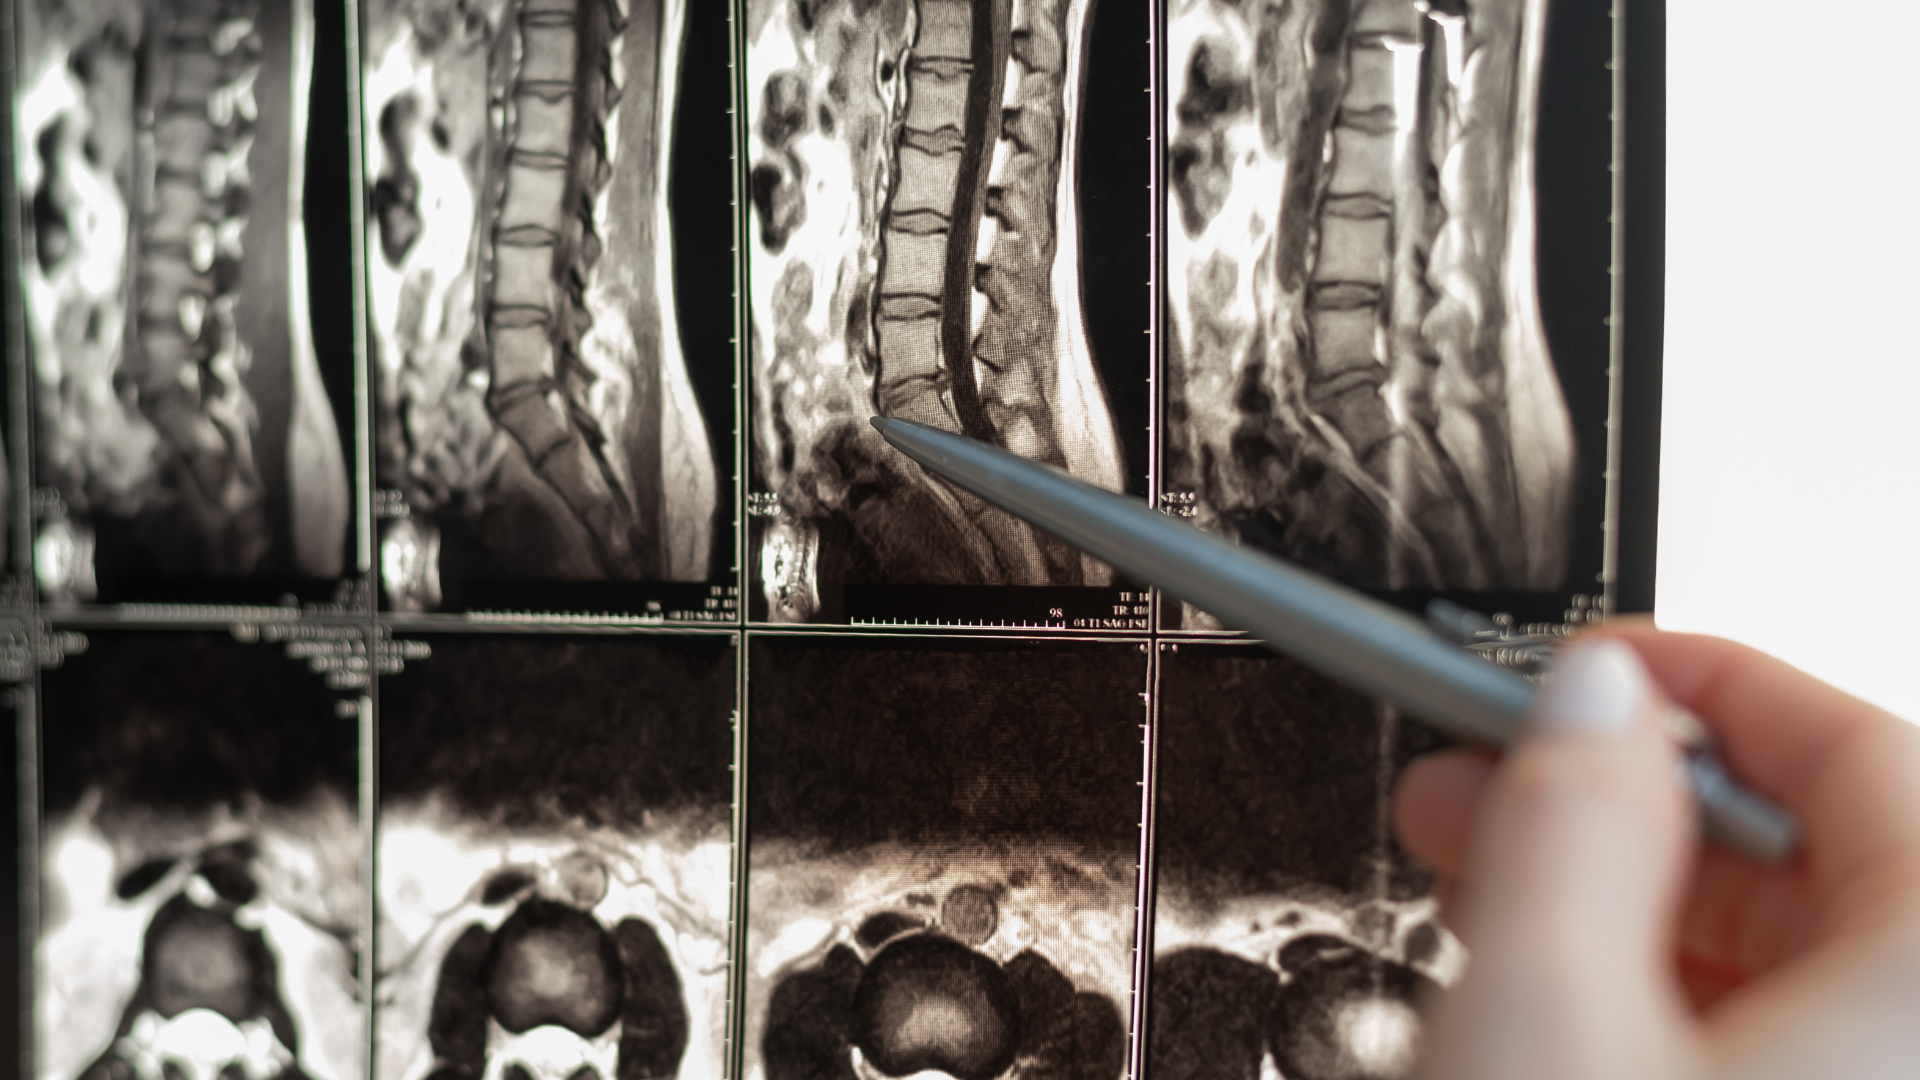

Diagnosing lumbar spinal stenosis and sciatica typically involves a thorough medical history, physical examination, and imaging studies such as X-rays, MRI, or CT scans. Treatment options for these conditions may vary depending on the severity of symptoms and underlying causes.